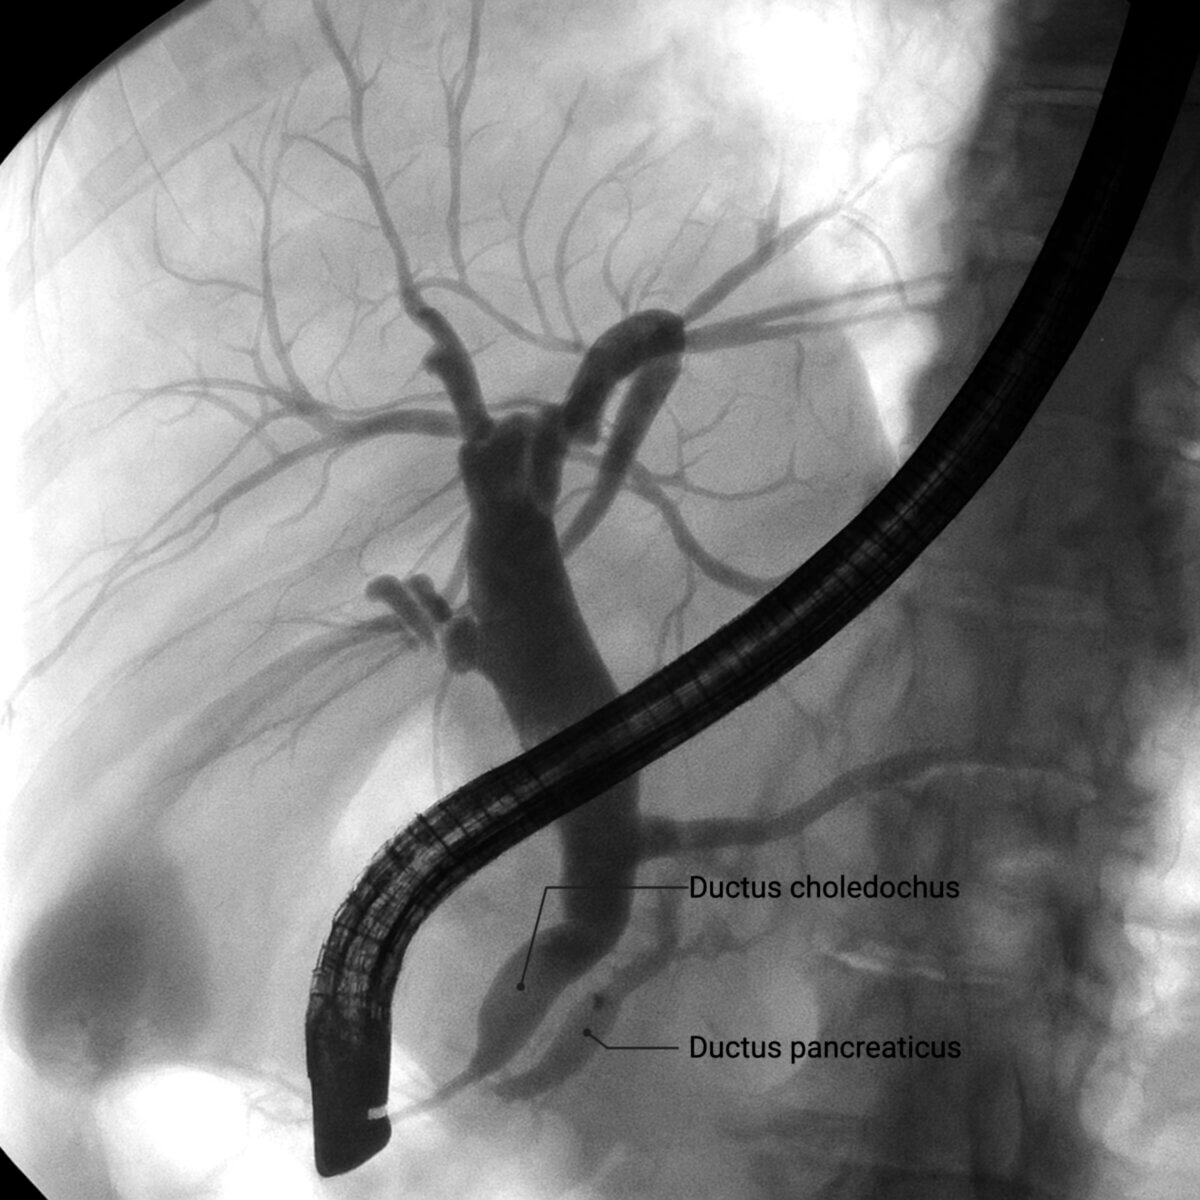

Das Double-Duct-Zeichen ist ein radiologisches Zeichen, das die gleichzeitige Dilatation des Ductus choledochus und des Ductus pancreaticus beschreibt. Es tritt typischerweise bei einem mechanischen Hindernis im Bereich der Papilla vateri auf, wie bei einem Pankreaskopfkarzinom oder einem distalen Gallengangskarzinom.

Das Double-Duct-Zeichen kann in einer ERCP-, CT- oder MRT-Untersuchung oder bei der Sonographie auftreten.

KI-generierte Darstellung einer ERCP mit double-duct Zeichen